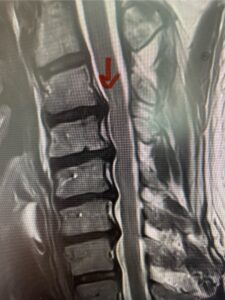

In this next case, this patient is a 47 year-old female who presents with intractable low back pain with severe pain, numbness, and weakness in the right lower extremity that had gotten progressively worse over a year. The patient had failed conservative management including physical therapy and epidurals. She was noted to have ⅘ weakness of plantar flexion. MRI demonstrated a large right L5-S1 disc herniation with severe compression of the descending right S1 nerve root (Fig 3). It was decided to perform a right L5-S1 hemilaminectomy for removal of the disc fragment and decompress the S1 nerve root. When you expose the disc, one must be certain to release any anterior adhesions to the nerve root in order to prevent a dural tear during retraction of the nerve root. It is also important to make sure during exposure and you finally encounter the dura after removing the ligamentum and fat, to make sure you are looking at the nerve root and not the main trunk of the thecal sac because if you don’t you can avulse or damage the nerve root if you retract the wrong structure.

Fig. 3a: Sagittal and axial T2-weighted lumbar MRI images demonstrating large right L5-S1 disc herniation (red arrows)

We found a massive subligamentous herniation which had to be revealed by having your partner retract the freed nerve root with a nerve root retractor and putting slight downward pressure on the more medial and anterior disc space. There is nothing more satisfying when the jelly (disc fragment) of the annulus (donut) comes squirting out and you remove a large chunk of disc material that clearly was stretching the ligament membrane and compressing the nerve root. This does cause back pain in addition to radiculopathy not only by the component of mechanical compression but also the stretching of the nerves within the ligament. We performed this surgery and noted that the nerve root was a very angry red color or hyperemic and we removed a large subligamentous fragment. The patient had improvement of her preoperative radicular symptoms.